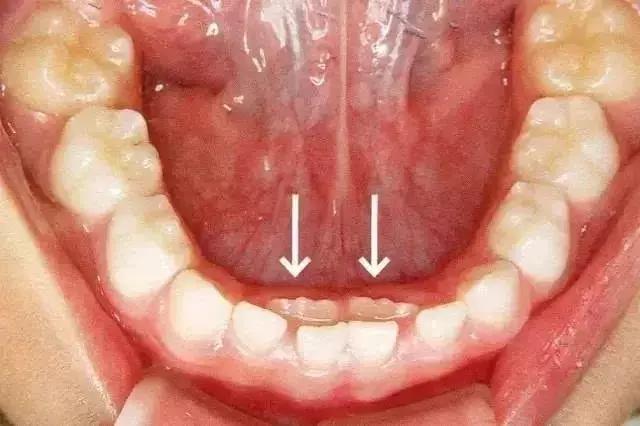

这种孩子乳牙还没脱落,新牙就长出来的现象,就是所谓的“双排牙”现象。也就是医生常说的“乳牙滞留”。

箭头所指为恒牙

1. 继承恒牙已经萌出,而乳牙未脱落,称早期滞留;

2. 恒牙未萌出,但已超过正常换牙年龄极限仍未脱落的乳牙,称晚期滞留。